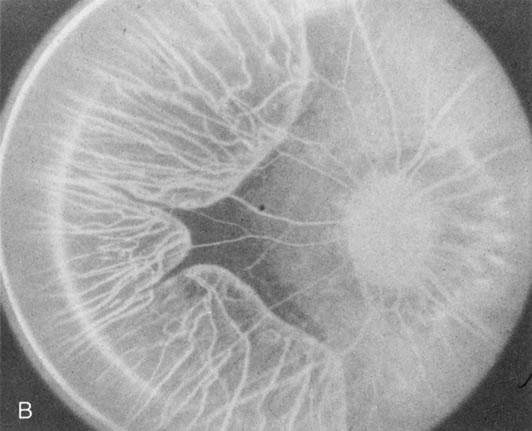

Generalized choroidal dystrophy is usually noted in middle-aged mildly symptomatic individuals who show a predominantly peripapillary or pericentral distribution of choroidal atrophy. Gradually, over the years these areas enlarge to eventually involve the entire retina. These changes are vividly seen on FA (Fig. 6).

Fig. 6. Generalized choroidal dystrophy. This 65-year-old woman gradually developed enlarging, progressive areas of choroidal atrophy over a 20-year period. When initially seen, the abnormalities were confined to the peripapillary and macular region (A,B). In a recent examination, the generalized choroidal atrophy is vividly demonstrated on angiography (C–F).